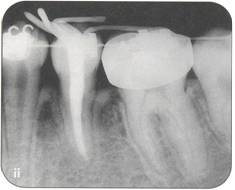

Fi 545e45f g 5-2a Panoramic view on first visit of a nineteen-year-old female patient. The maxillary right third molar will be transplanted to the area of the nonrestorable mandibular right first molar. |

Fi 545e45f gs 5-2b and 5-2c Preoperative view of the maxillary and mandibular arches. |

Fi 545e45f gs 5-2d and 5-2e Preoperative view of the tooth to be extracted. |

Fi 545e45f gs 5-2f and 5-29 Preoperative view of the donor tooth. |

Fi 545e45f g 5-2h Extracted donor tooth. This tooth seems to be at developmental stage 6. |

Fi 545e45f g 5-2i The recipient site right before transplant procedure (2 weeks after extraction of the first molar). |

Fi 545e45f g 5-2j After suturing of the gingival flap and fixation of the donor tooth using sutures. |

Fi 545e45f g 5-2k After transplantation. |

Fi 545e45f g 5-21 Two months after transplantation. |

Fi 545e45f g 5-2m Two months after transplantation. In a developing tooth, pulpal healing is expected. One must, however, carefully watch for signs of resorption or development of bony lesions indicating pulp necrosis. |

Fi 545e45f g 5-2n Eight months after transplantation. Obliteration of the pulp canal from the apex has begun, indicating pulpal vitality. |

Fi 545e45f g 5-20 Two years 5 months after trans. plantation. Total obliteration of the pulp canal has occurred, which is a normal outcome. |

Fi 545e45f gs 5-2p and 5-2q Two years 5 months after transplantation. The donor tooth is restored with composite resin. |